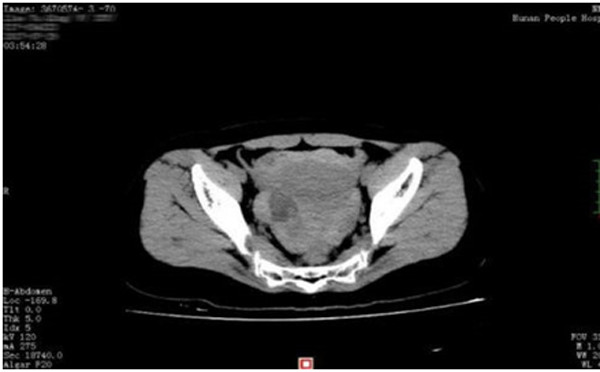

Hình ảnh siêu âm khối u xơ tử cung, u nang buồng trứng bị vỡ